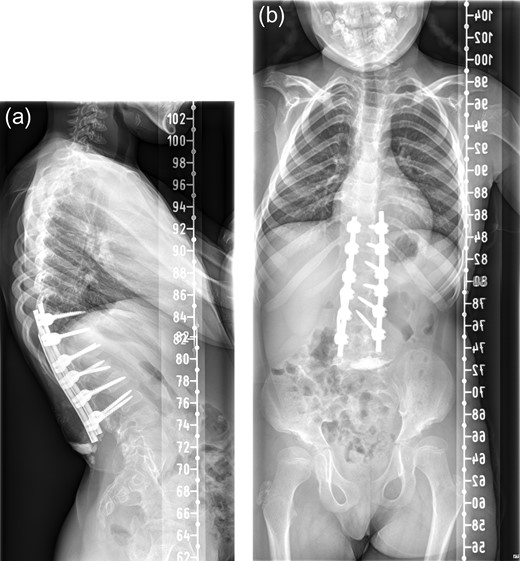

An 8-year-old girl with Mucopolysaccharidosis 1 and high lumbar kyphosis (Fig. 1) was admitted for posterior spinal fusion. Surgery was performed in prone position with multimodality spinal cord monitoring using a posterior midline approach. Spinal fixation was done with pedicle screws from T10 to L3 vertebrae. Spinal osteotomies were performed and kyphosis was corrected. It is the senior surgeon’s preference to augment fusion with i-Factor in order to promote early fusion in this patient group. Two 50 mm i-FactorTM bone graft Flex FR strips were cut along their length, one half was placed medial to the implants over the lamina and the other half placed lateral to the implants in posterolateral gutter. Allograft was placed on top of the strips. Wound was closed in layers leaving behind a drain over the fascia.